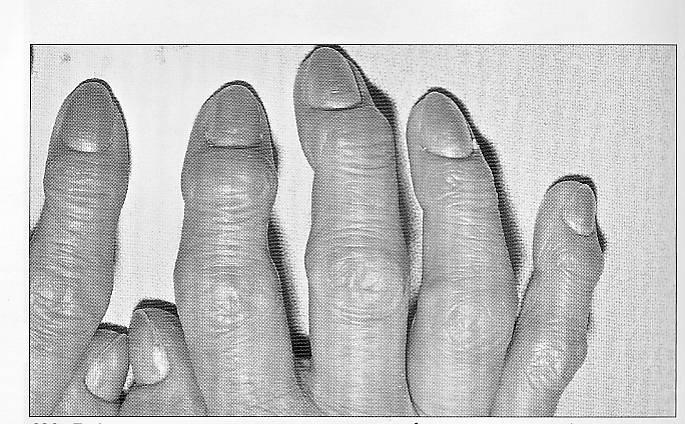

Симптомы и лечение остеоартроза узелков Гебердена: фотогалерея